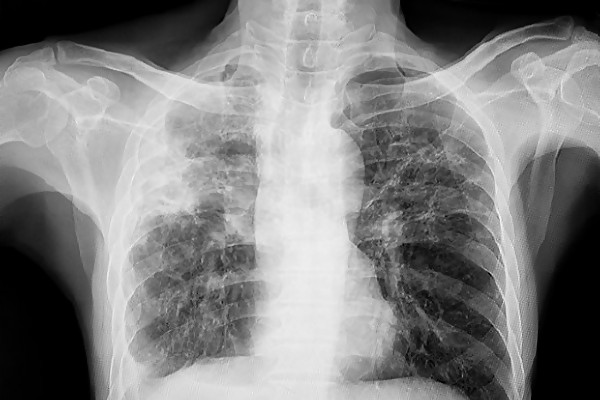

Европа изостава в борбата с туберкулозата: Всеки пети случай остава неоткрит

Европейският регион продължава да изостава от поставените цели за ограничаване на туберкулозата, показва нов съвместен доклад на Световната здравна ...